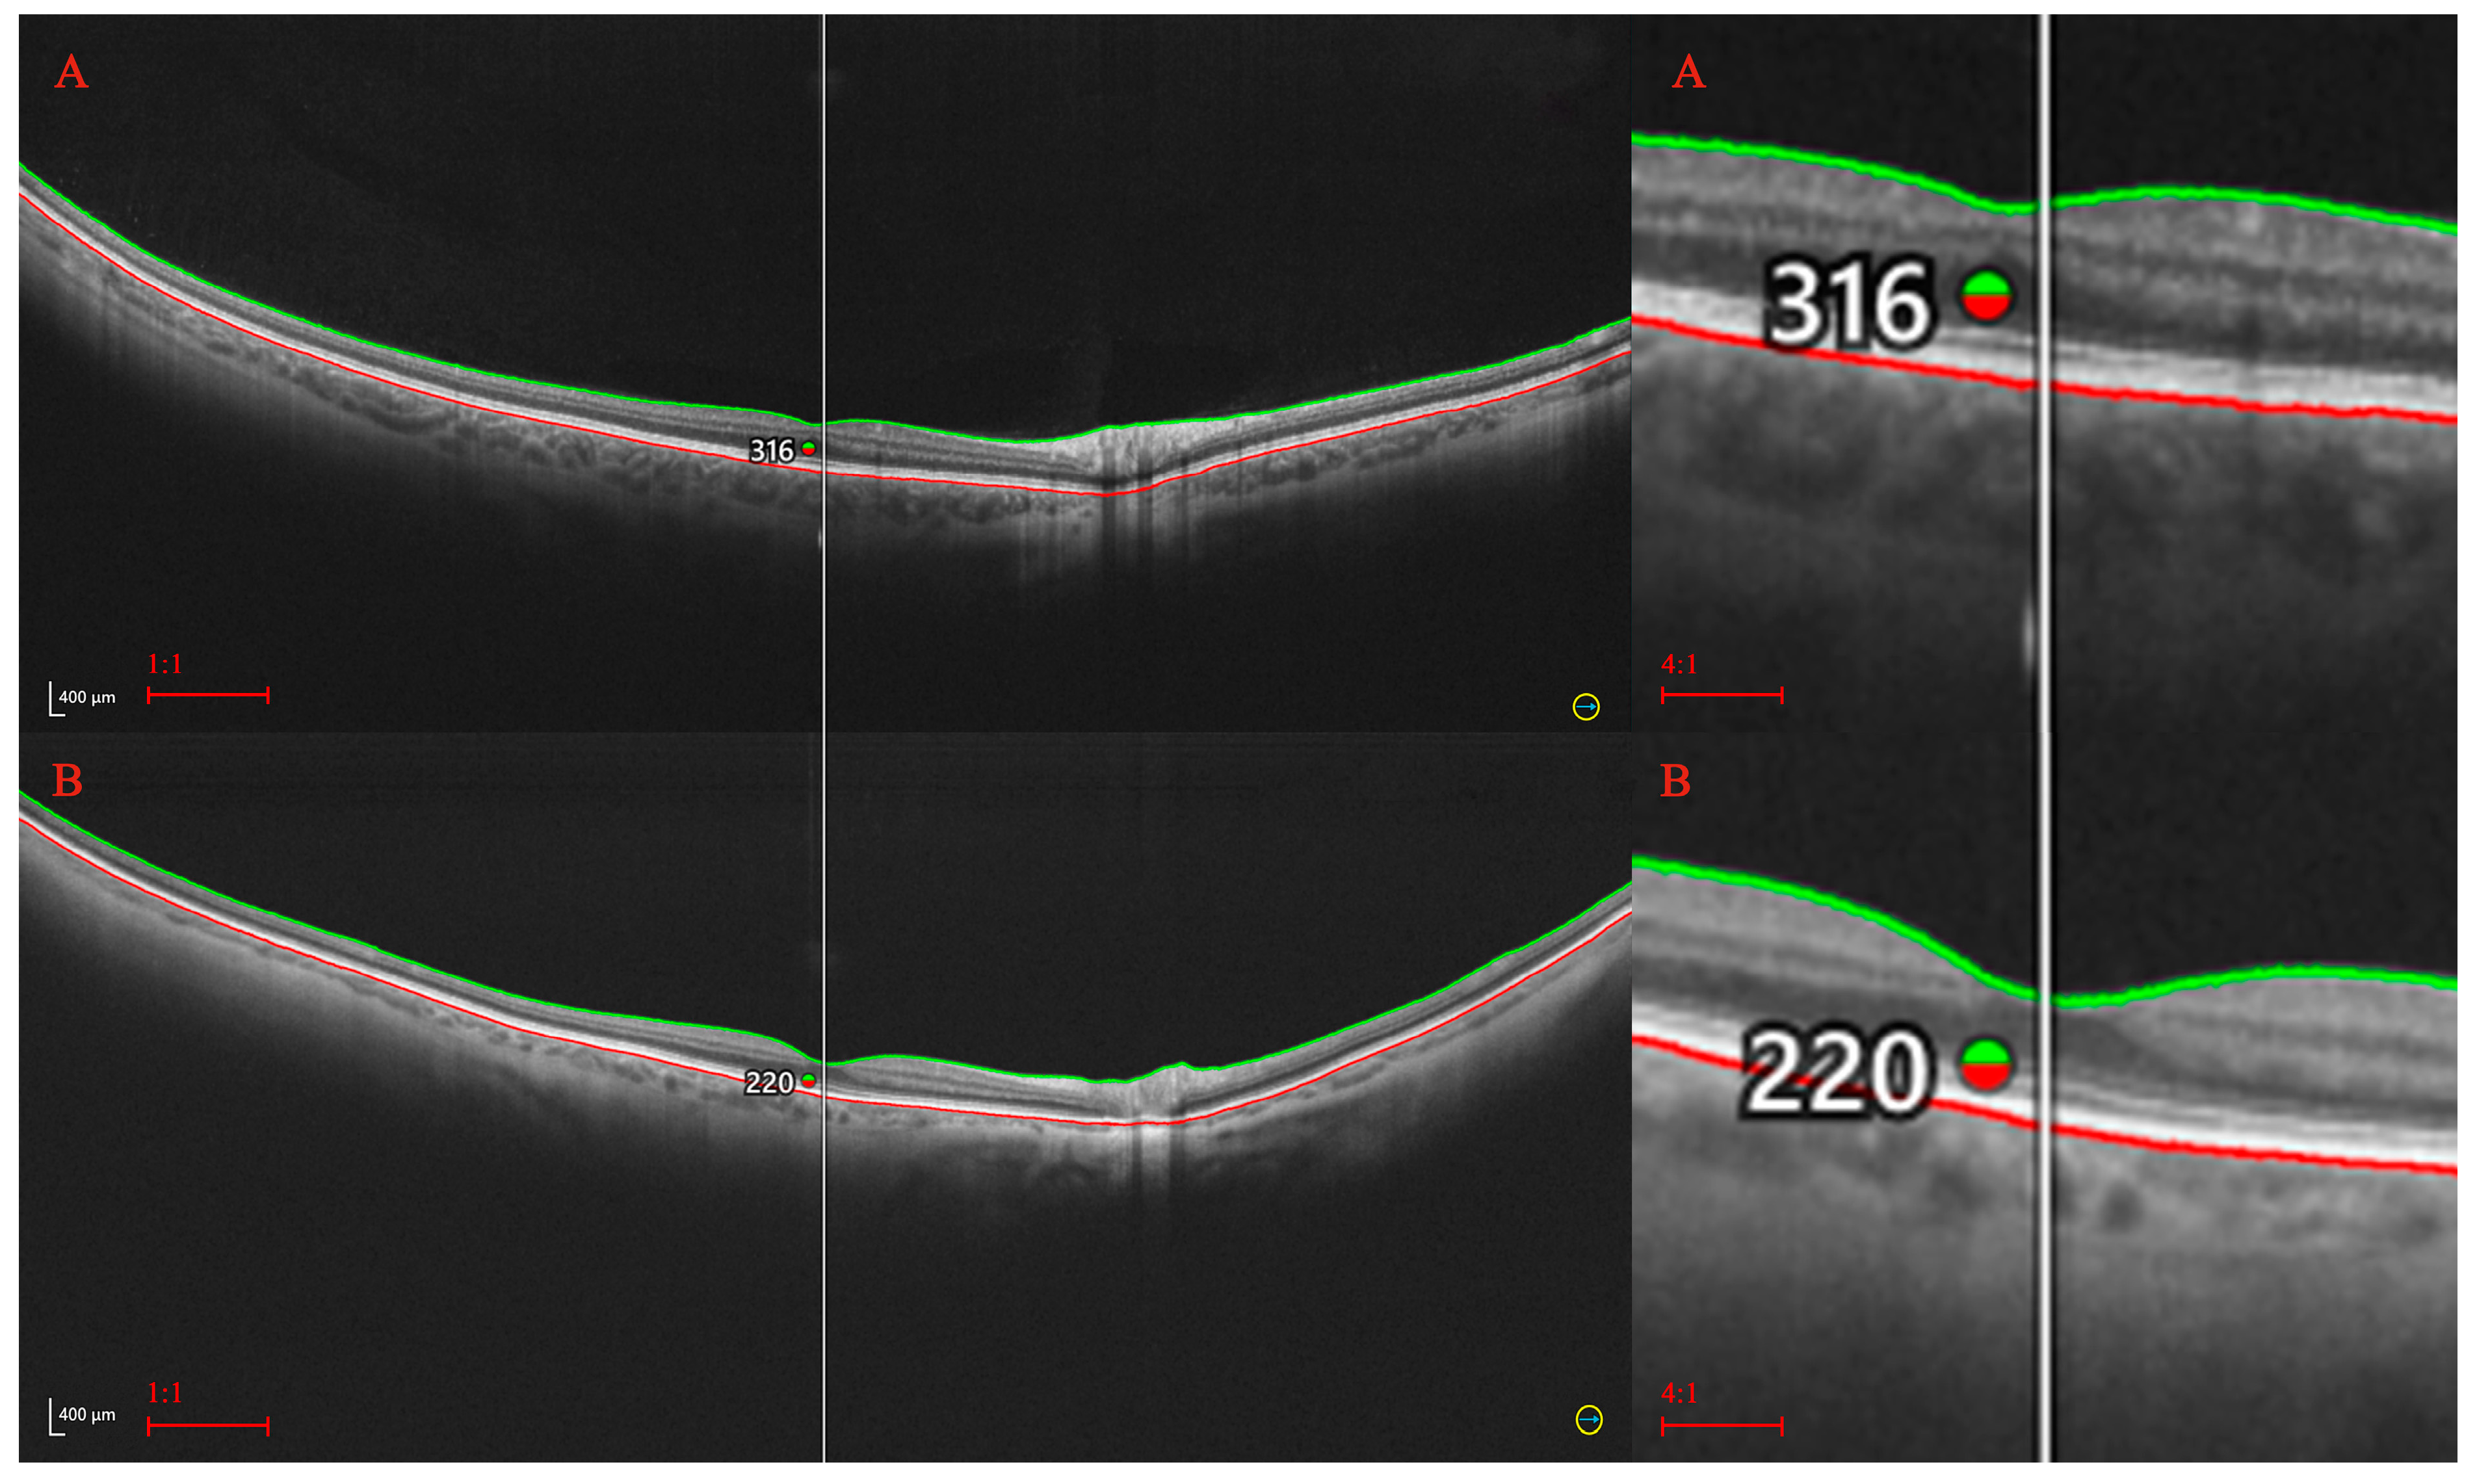

2. Materials and Methods